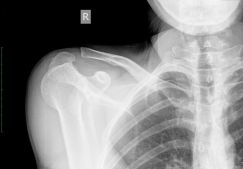

Диагноз выставляется на основании осмотра травмированной ноги и жалоб пациента. Проводится ряд инструментальных исследований (МРТ, электромиография) для оценки состояния мышц и расположенных рядом связок, сухожилий, мягких тканей. При незначительном повреждении лечение консервативное. Для восстановления сильно травмированных мышц требуется хирургическое вмешательство.

Клиническая картина

Первым симптомом растяжения мышц коленного или голеностопного сустава является сильная, пронизывающая боль. Она настолько острая, что возможна потеря сознания. Особенно опасен болевой шок — патологическое состояние, угрожающее жизни пострадавшего из-за учащения сердцебиения, резкого падения артериального давления. В момент разрыва волокон может слышаться щелчок, напоминающий хруст переламываемой сухой палки. Раздражение рецепторов, усиление кровотока приводят к покраснению кожи в области повреждения. В течение нескольких часов возникают следующие признаки, характерные для растяжения мышц: